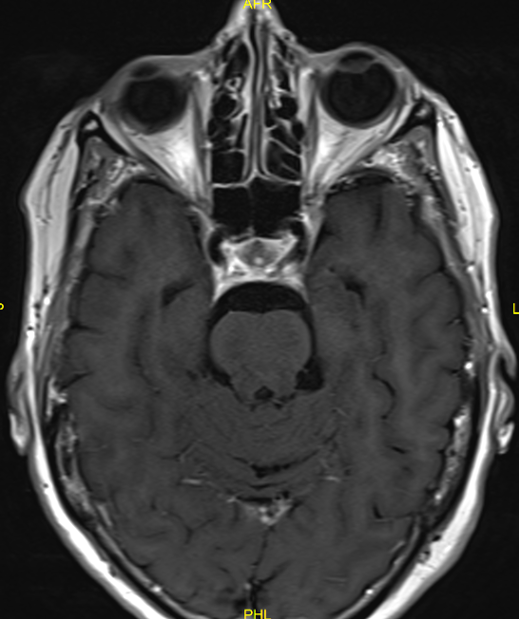

An urgent MRI with gadolinium contrast was performed and described a dural enhancement (5 mm thickness, antero-posterior (AP) over 2 cm) and dural tail sign at the left cavernous sinus in contact with the left internal carotid artery as with the left optic canal (Figure 2 [Fig. 2]). This new lesion was radiologically diagnosed as a meningioma and found to be explanatory for the third and fifth (V1) nerve palsy but was unable to explain the former cranial nerve palsies and had not been present at previous MRI scans, with and without gadolinium contrast (Figure 3 [Fig. 3]).

Figure 2: MRI scan (2017) showing dural enhancement at the left cavernous sinus

Figure 3: MRI scan (2014) at the level of the cavernous sinus

In patients presenting with recurrent cranial nerve deficits, the main differential diagnosis includes multiple sclerosis, neuroborreliosis, other central nervous system (CNS) inflammation or infection, increased intracranial pressure, lymphoma and neurosarcoidosis. Diagnostic testing includes serum and cerebrospinal fluid (CSF) analysis. Angiotensin converting enzyme (ACE) might be elevated but should not be regarded as a diagnostic test in patients with isolated neurosarcoidosis as it is nonspecific and not too sensitive [6]. It was not elevated in the discussed case. MRI is the gold standard for neurosarcoidosis imaging but may be negative, especially in non-enhanced imaging studies [2]. A wide range of findings has been described in neurosarcoidosis [7]. In our case, gadolinium-enhanced MRI showed a dural enhancement in the left cavernous sinus at the time of the third cranial nerve palsy. This lesion was radiologically diagnosed as a meningioma due to the characteristic imaging properties and a ‘dural tail’ sign (DTS). Initially regarded as pathognomic for a meningioma, it has become increasingly noted that the DTS can be present in many other conditions like dural sarcoidosis [8]. In the brain, leptomeningeal and dural sarcoidosis is seen in approximately 40% of patients with neurosarcoidosis [9], [10]. The cranial nerves may become involved via perineural spread from adjacent sites. The close proximity of the meninges in the cavernous sinus explains why the involvement of the cranial nerves is often in this location. Dural sarcoidosis and leptomeningeal involvement, although not typically combined, present with similar symptoms relating to cranial nerve involvement if present and more general symptoms like fatigue and headache [11]. The patient in this case complained of a headache, but this is a nonspecific symptom [2]. Imaging in dural sarcoidosis characteristically shows isointense diffuse dural thickening or focal dural masses on unenhanced T1-weighted images and hypointensity on T2-weighted images. Enhancement can be seen on gadolinium contrast-enhanced T1-MRI [7], [9]. This enhancement on T1-weighted image was seen in the discussed case. Unfortunately, these imaging characteristics are nonspecific and insufficient to differentiate neurosarcoidosis from other dural diseases including meningioma [9], [11]. There is a number of published cases of neurosarcoidosis mimicking meningioma on imaging studies, as occurred in the discussed case [11]. Accurate diagnosis is of great importance, since neurosurgical procedures can be avoided.